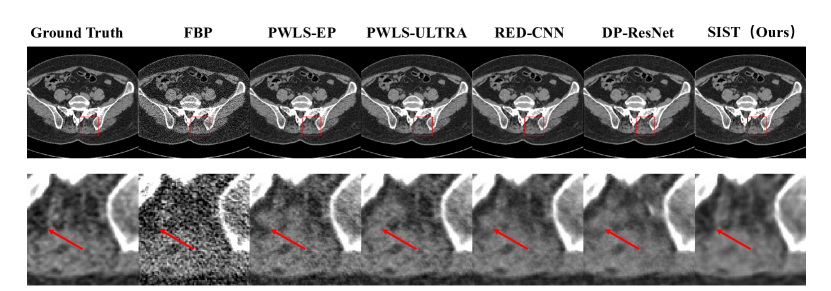

Refer to caption

Figure 9: Visual results of ablation study that verify the effectiveness in sinogram domain. We compare the sinogram domain denoising performance with a CNN-based U-Net, a single sinogram transformer, and our proposed method which uses the sinogram transformer with inner-structure loss. We reconstruct images of all three methods using FBP. The first row shows the reconstructed images. ROIs in the red box are zoomed in the second row. The third row shows the sinogram difference with ground truth (the bluer, the better).

4.4 Ablation Study

To further explore the effectiveness of different components, we conduct the ablation study in this section.

4.4.1 Effectiveness in Image Domain

Compare to typical deep learning methods, the proposed framework focuses on the inner-structure of the sinogram to improve the image domain denoising quality. So, one important question is that how much does the inner-structure impact the image quality? Tab.3 shows results of using different components. We first remove all sinogram domain components and use the rest part (U-Net) to train and test only in the image domain. Without any specific design, the PSNR achieves 38.09 dB𝑑𝐵dB of pure U-Net CNNs. After we add the sinogram denoising transformer and image reconstruction module, the performance improved significantly in all three metrics. To further utilize the inner-structure of the sinogram, the global inner-structure loss is added to utilize conjugate projection pairs in the sinogram. This loss helps improve the performance as shown in Tab.3. At last, we add the local inner-structure loss to maintain the second-order sparsity of the sinogram, and the performance is further improved.

4.4.2 Effectiveness in Sinogram Domain

In this part, we verify the effectiveness of our method in improving the sinogram denoising. For comparison, we use the U-Net and sinogram transformer module to train with low-dose/normal-dose sinogram pairs. Since we care more about the quality of reconstructed images, we evaluate sinograms by applying FBP reconstruction. Note that our proposed method use end-to-end training to directly get the reconstructed image. For a fair comparison, we still apply FBP on the intermediate sinogram output. Fig.9 shows the example of the results. As we can observe, even though all the denoised sinograms are of high similarity to the ground truth, there still are obvious artifacts in reconstructed images. Compare to the CNN-based U-Net, the sinogram transformer can better extract the structure information in the sinogram and improve the quality. By further adding the inner-structure loss of sinogram, artifacts in images are considerably reduced.